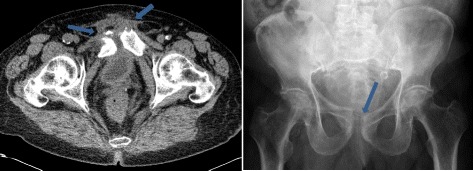

As his mobility steadily decreased and he had massive pelvic pain in the following weeks, a ring fracture of the pelvis, most probably on the basis of the destabilizing recurrent symphysitis, was diagnosed radiologically (Figs. 3 and 4).

Fig. 3.

Symphysitis (computed tomography scan, left) and dilatation of the symphysis fissure and osseous erosions (conventional radiography, right) (arrows)